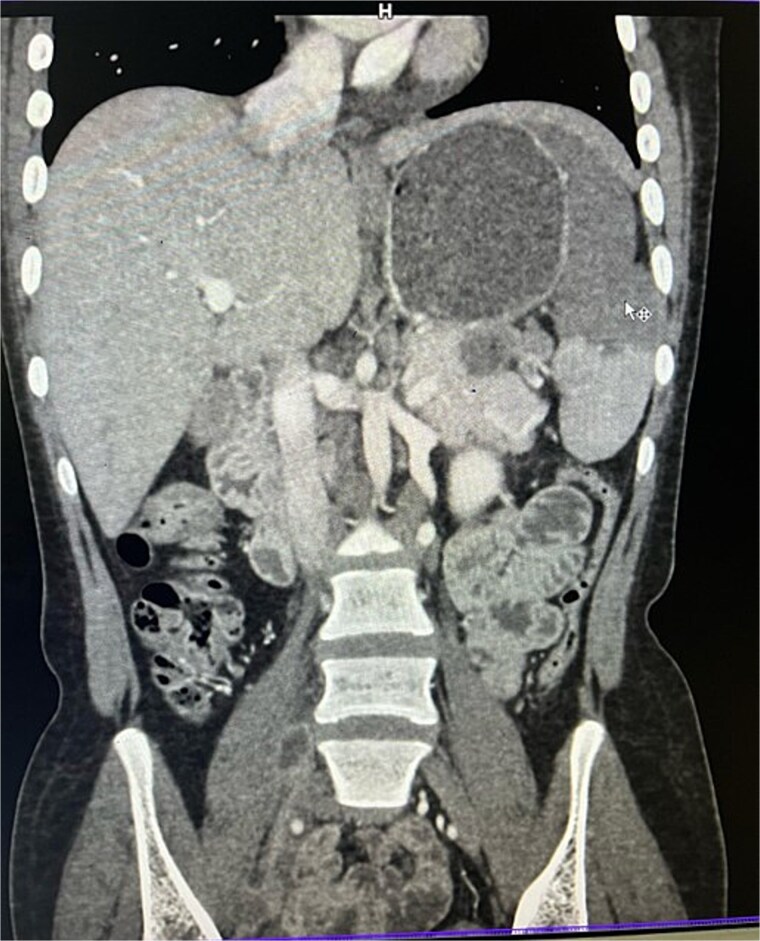

腹结核(TB)是一种罕见的肺外表现,累及胰腺和脾脏极为罕见,常被误诊为恶性肿瘤。我们提出的情况下,22岁的女性慢性胃痛,体重减轻,发烧。影像学显示胰腺尾部及脾门附近有坏死淋巴结肿块伴脾梗死。细针抽吸细胞学证实为结核病,患者对抗结核治疗反应良好,避免了手术干预。本病例强调了在流行地区的上腹部肿块鉴别诊断中考虑结核的重要性,以防止不必要的手术。

Abdominal tuberculosis (TB) is a rare extrapulmonary manifestation, with pancreatic and splenic involvement being extremely uncommon and often misdiagnosed as malignancy. We present the case of a 22-year-old female with chronic epigastric pain, weight loss, and fever. Imaging revealed a necrotic lymph node mass near the pancreatic tail and splenic hilum with splenic infarction. Fine-needle aspiration cytology confirmed TB, and the patient responded well to anti-tubercular therapy, avoiding surgical intervention. This case underscores the importance of considering TB in the differential diagnosis of upper abdominal masses in endemic regions to prevent unnecessary surgeries.